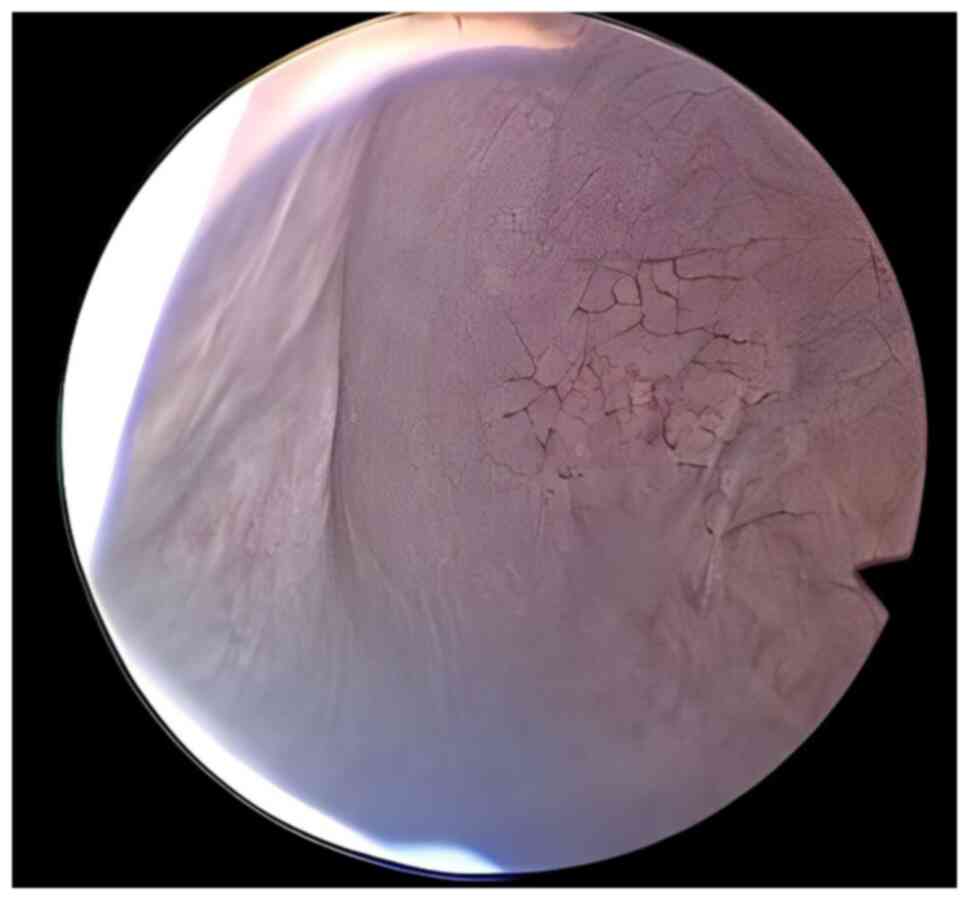

Bladder leiomyoma in the absence of symptoms: A case report and mini‑review of the literature

Figure 4